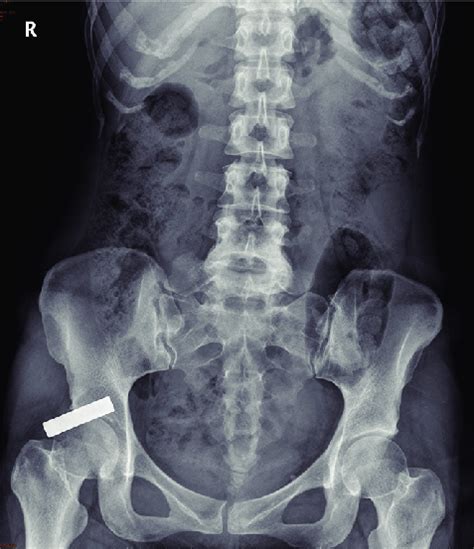

Unremarkable Bowel Gas Pattern

Abdominal plain film with 'unremarkable' gas pattern (on retrospective